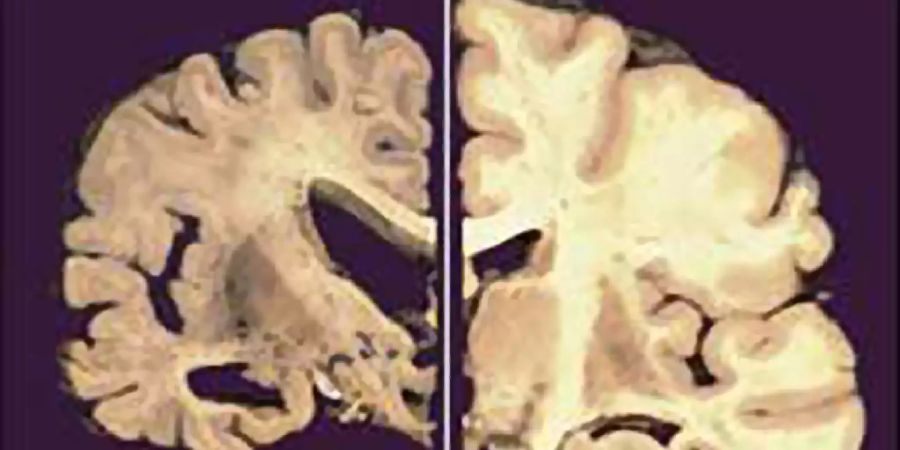

Männerhirne schrumpfen schneller als Frauenhirne. Forschende aus Oslo liefern neue Einblicke in geschlechtsspezifisches Altern.

Eine internationale Untersuchung der Universität Oslo hat deutliche Unterschiede zwischen männlichen und weiblichen Gehirnen festgestellt. Über 12'000 MRT-Scans von Personen zwischen 17 und 95 Jahren zeigen, dass Männer in deutlich mehr Gehirnregionen Volumen verlieren.

Der Rückgang betrifft laut der Studie grosse Teile des Kortex, wie «IT Boltwise» berichtet. Frauen wiesen dagegen geringere Veränderungen in der Dicke dieses Bereichs auf.

Trotz der höheren Alzheimer-Rate unter Frauen scheinen weibliche Gehirne also strukturell stabiler zu altern.